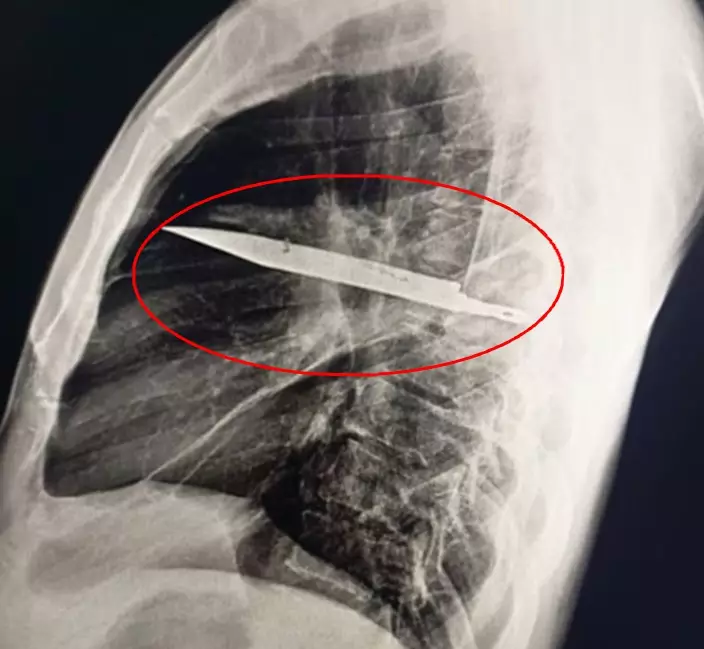

胸部X光檢查揭開謎底,影像清楚顯示有一把刀埋在患者胸腔內,神奇的是這把刀從右肩胛骨刺入,奇蹟般避開所有重要器官。

坦桑尼亞44歲男乳頭痛流膿,醫生檢查驚揭胸腔插刀8年。圖片來源:外科病例報告期刊